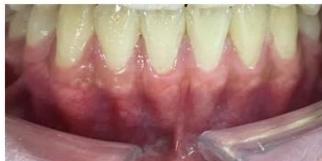

Figure 2: Pre-Treatment Intraoral Photographs

Intraoral examination revealed severe proclination and protrusion of both the maxillary and mandibular incisors [6]. The occlusal relationship was Class I at the canine (tooth 3) and first molar (tooth 6) levels bilaterally. A critical unfavorable biological factor was the proximity of the mandibular incisor roots to the labial cortical plate, representing a high-risk condition when planning extraction-based anterior retraction mechanics [10-12]. All four third molars were present.